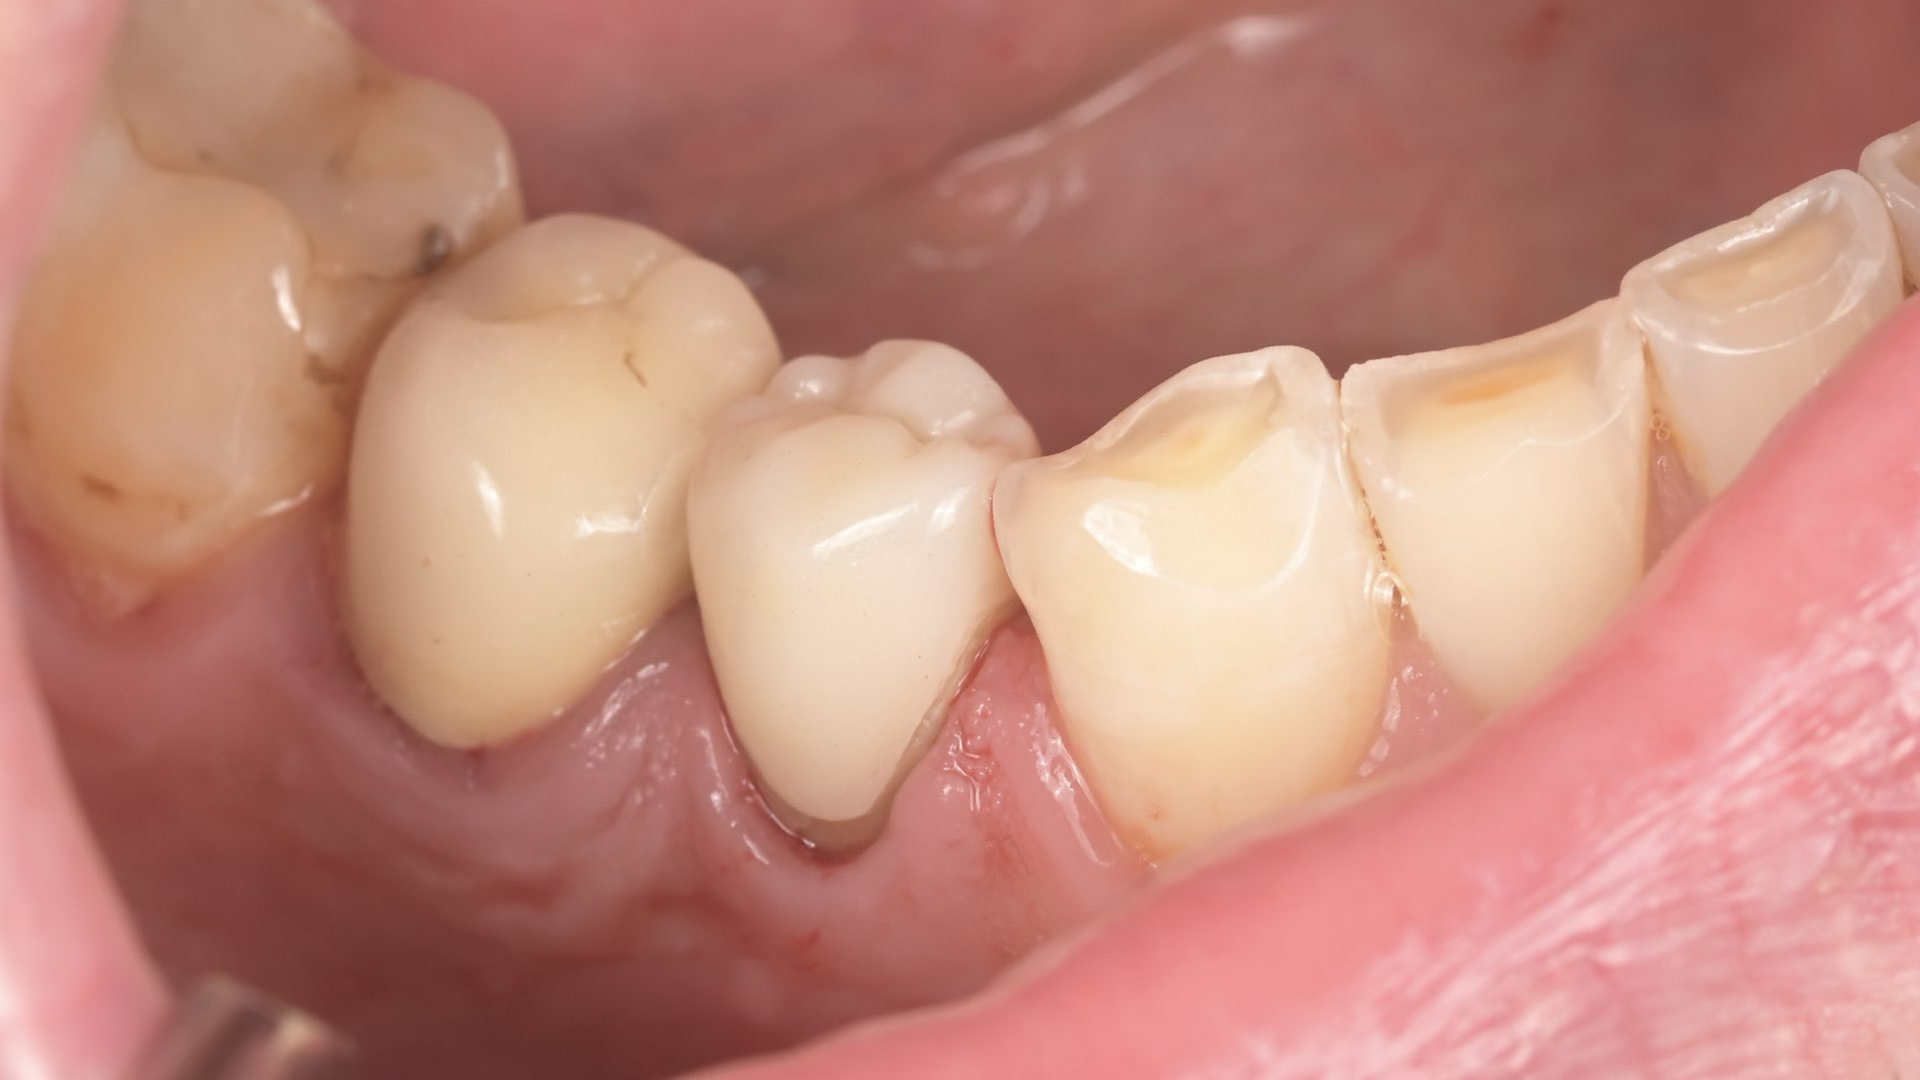

A biomimetikus fogászat egy modern megközelítés, melynek célja, hogy a fogak helyreállítását a fogorvos a természetes fog szerkezetét utánozva végezze el. A módszer kulcsa, hogy a fogat a lehető legkevésbé invazív módon kezelje, maximalizálva a megmaradt egészséges fogszövetet.

Célja, hogy az elkészült tömések és betétek (inlay, onlay) ugyanolyan erősek és rugalmasak legyenek, mint a természetes fog.

Ennek eléréséhez speciális ragasztási technikákat és bio-kompatibilis, üvegszál-erősítésű anyagokat használnak, melyek szorosan kötődnek a foghoz.

A hagyományos koronázással szemben, ahol sok ép foganyagot kell eltávolítani, a biomimetikus eljárásnál csak a sérült részeket távolítják el.

Ez segít megelőzni az úgynevezett „mély tömések” okozta gyökérkezelési szükségletet, mivel az ideg a fogban kevésbé sérül.

A megmaradó erős fogszövetnek köszönhetően a helyreállított fogak sokkal ellenállóbbak a repedésekkel és töréssel szemben.

A rágóerők egyenletesebben oszlanak el, így a fogat kevesebb stresszhatás éri rágás közben.

Ez a megközelítés hosszú távon stabilabb és tartósabb eredményt biztosít, csökkentve a jövőbeni fogászati beavatkozások szükségességét.

Összefoglalva: Az így elkészült tömések időtállóbbak, pontosabbak és jobban védik a megmaradt foganyagot, mint a hagyományos technikával elkészített tömések, a kutatások alapján, ez a jelenlegi ismereteink szerinti legmodernebb, evidence-based eljárás.